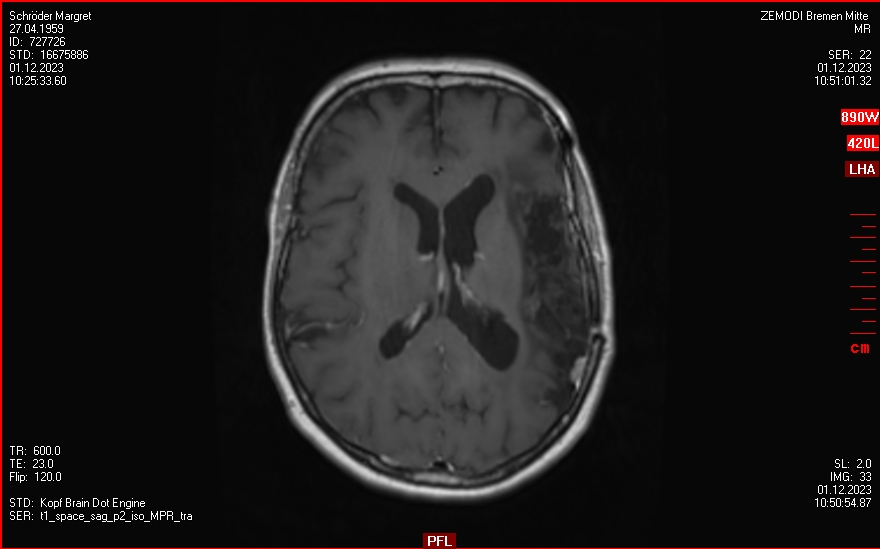

bis Mitte 2023

Regelmäßige Kontrollen, kleine Rezidiv-Funde aber keine Empfehlung für eine Behandlung.

Sommer 2023 - Ende 2023

Ein paar Anfälle incl. Notaufnahme im Krankenhaus.

Aber keine Info aus der Tumorkonferenz.

04.12.2024

OP im Krankenhaus Bremen-Mitte: 4 Menigeome (WHO III) entfernt, einige weitere verbleiben.